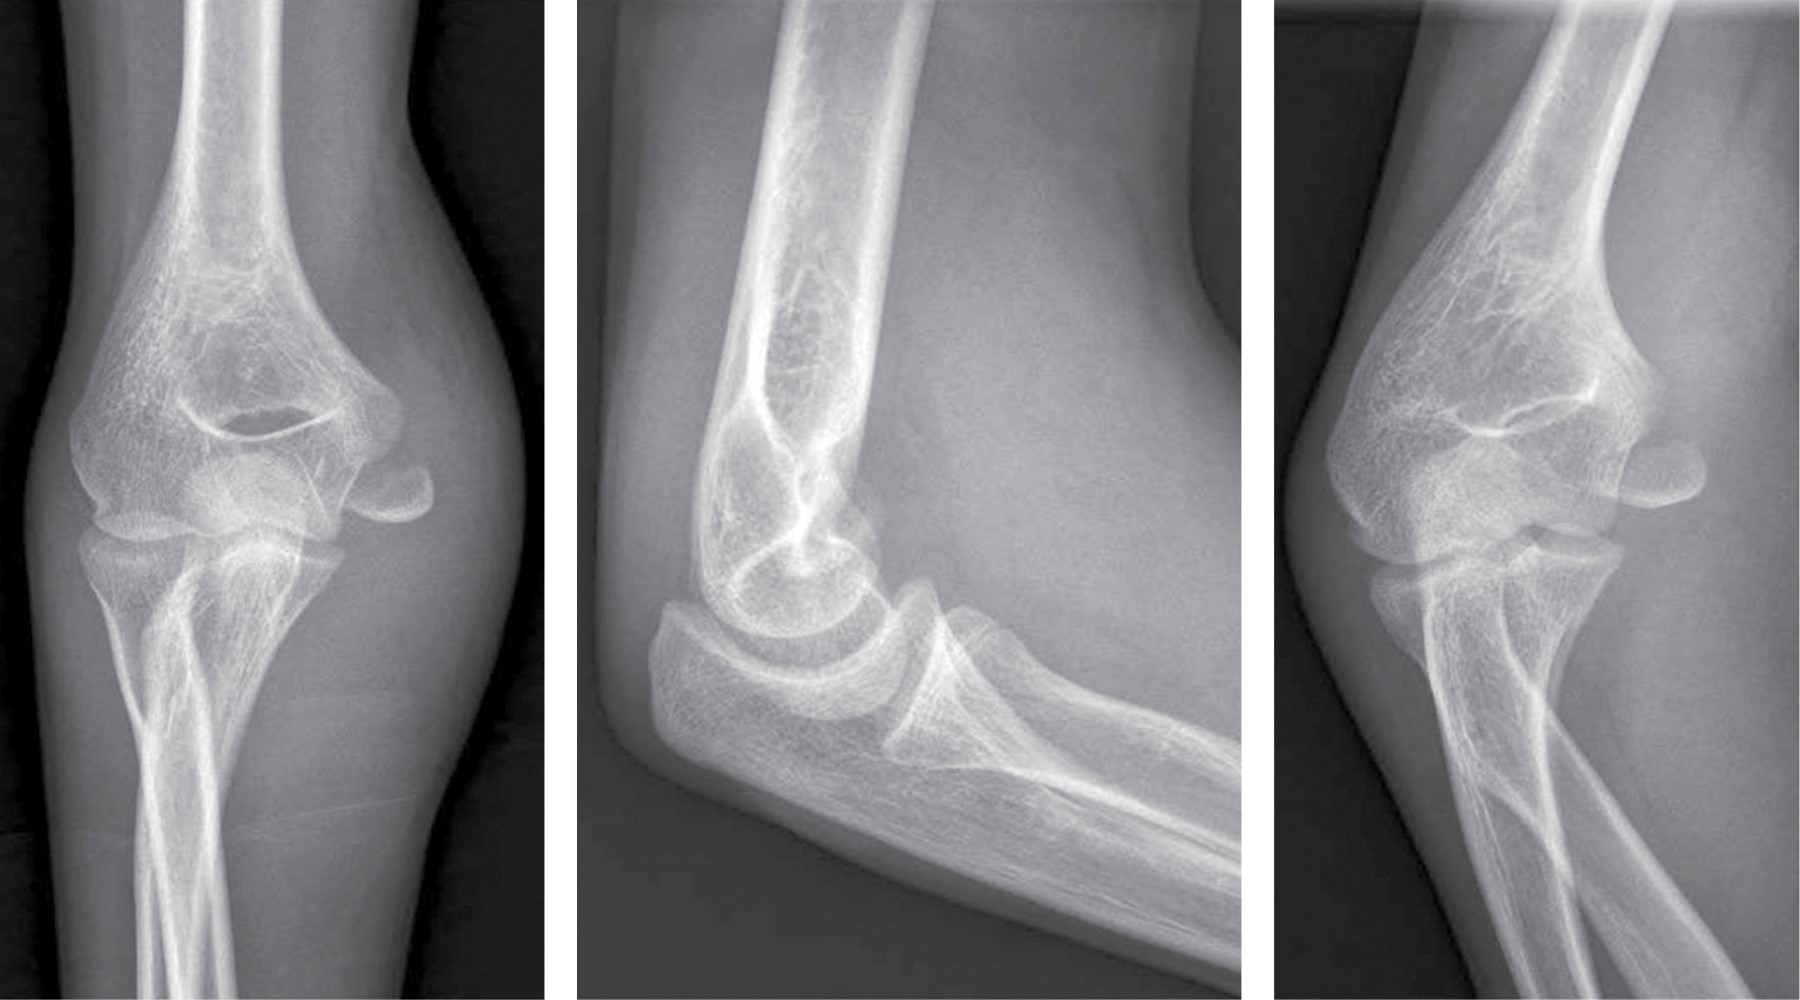

Masculino 15 años - fractura diafisaria desplazada de radio y cúbito (Figura 1).

• 1. Fijación con clavos elásticos – Dr. Andrés Ferreyra (SAOTI):

Las fracturas de antebrazo ocurren aproximadamente en uno de cada 100 niños, y representan la tercera fractura más común en los huesos largos en este grupo etario. Su incidencia máxima es entre los 12 y 14 años. Actualmente el tratamiento habitual se divide entre la inmovilización con yeso y la estabilización con clavos elásticos o placas y tornillos, los cuales predominan en pacientes de mayor edad o con fracturas inestables.7,8